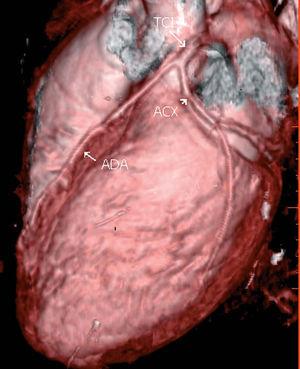

Se muestran las imágenes del árbol coronario que permiten descartar anomalías en esta localización. La figura 1 muestra una proyección axial de máxima intensidad (MIP) de la salida de las arterias coronarias. La figura 2 es una proyección coronal de máxima intensidad (MIP) de la arteria coronaria derecha similar a la proyección oblicua anterior derecha de la angiografía. Las figuras 3 y 4 son reconstrucciones en volume rendering en proyección oblicua anterior izquierda del tronco coronario izquierdo y su bifurcación y de la base del corazón, en la que se visualiza la salida del tronco coronario izquierdo. Se han retirado las venas pulmonares izquierdas. En la estación de trabajo, mediante el análisis avanzado de vasos se puede visualizar un vaso tortuoso o de trayecto curvo en un solo plano tomográfico permitiendo una cuantificación de la lesiones estenóticas. El estudio no detectó anomalía en la anatomía ni estenosis coronaria significativa en el paciente.

Figura 1. Proyección axial de máxima intensidad de la salida de las arterias coronarias. ADA: arteria coronaria derecha; TCI: tronco coronario izquierdo.

Figura 3. Reconstrucción en volume rendering en proyección lateral izquierda del tronco coronario izquierdo y su bifurcación. ADA: arteria coronaria derecha; TCI: tronco coronario izquierdo; ACX: arteria circunfleja.